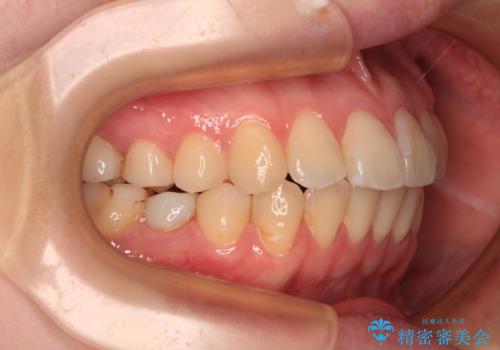

開咬と前方に飛び出した前歯 インビザラインによる矯正治療

- 上下前歯の非接触と叢生を気にして来院された患者様です。

開咬の改善はインビザラインの最も得意とするところであるため、インビザラインを用いて矯正治療を行うこととしました。

舌の突出癖改善のトレーニングをしっかりと行っていただき、上下前歯が接触する咬み合わせを達成することができました。